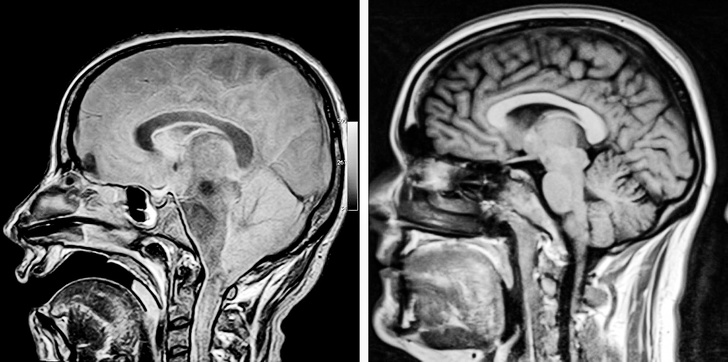

We can spend hours and hours reading books on anatomy to learn more about our body but what’s more eye-opening are a series of MRI scans and X-rays that precisely shows our body.